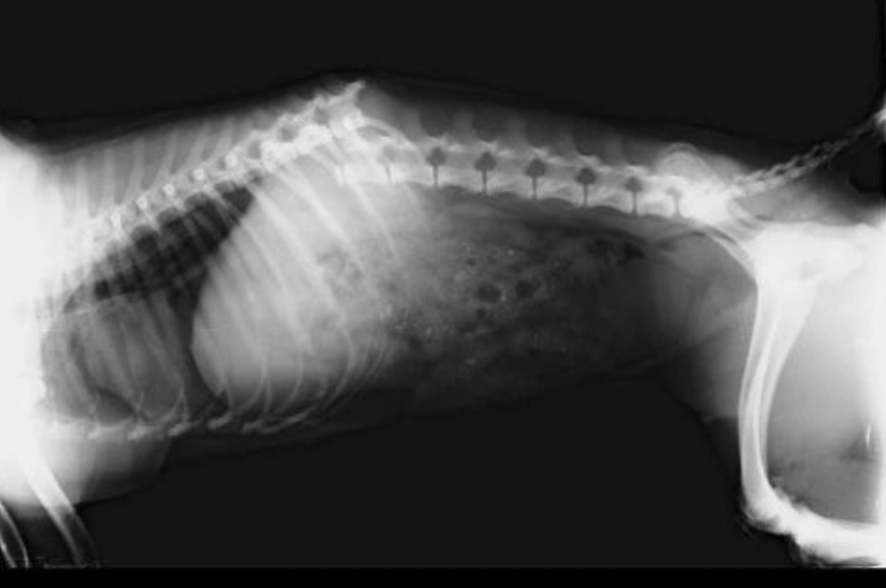

Tak terasa ada 283 ekor anak kaki empat yang tinggal bersama Ci Fang Fang saat ini. Anjing yang beliau selamatkan bukan hanya yang ‘dibuang’ oleh pemiliknya saja, tapi juga beliau selamatkan anjing yang terlantar di jalanan. Jadi tak heran kalau anak kaki empat di rumah ini lebih banyak anjing domestik dibanding anjing ras.

Ada juga anak kaki empat korban tabrak lari hingga alami patah tulang di punggungnya. Dokter pun sampai menyerah saat itu, suata ‘kaing kaing’ melengking kesakitan buat Miracle tak bisa apa-apa. Hanya tengkurap pasrah.

Tak hanya itu, banyak juga anak kaki empat disini yang menjadi korban kekerasan majikannya. Ada yang matanya sampai buta, kaki hanya 3, bahkan lumpuh.

“Semua anak anak ini sebetulnya sangat butuh untuk di vaksin pasca wabah scabies kemarin, karena jika tidak khawatir terkena lagi. Tapi apa daya.. Untuk ke dokter pun saya hanya bisa bawa anak yang benar-benar kondisinya parah kak, itupun harus menunggak, sampai sekarang tunggakannya sudah sangat besar..”